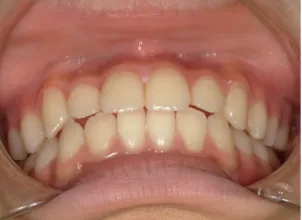

治療後⑩高2:17y7m 抜歯治療終了

口元の治療前後:15y5m→17y7m スッキリしました

| カウンセリング・診断結果 | 前歯が受け口になっていているため、適正な成長へ誘導するために前歯の咬み合わせの改善が必要なことを説明し、診断を希望されたので精密検査へ進みました。 精密検査の結果、骨格的には受け口傾向、下顎前歯の突出、上下ともアーチが小さく凸凹(叢生)が認められ、機能的には低位舌と口唇閉鎖不全があり、口元は上下唇とも突出していますがコンケーブになってないことがわかりました。 |